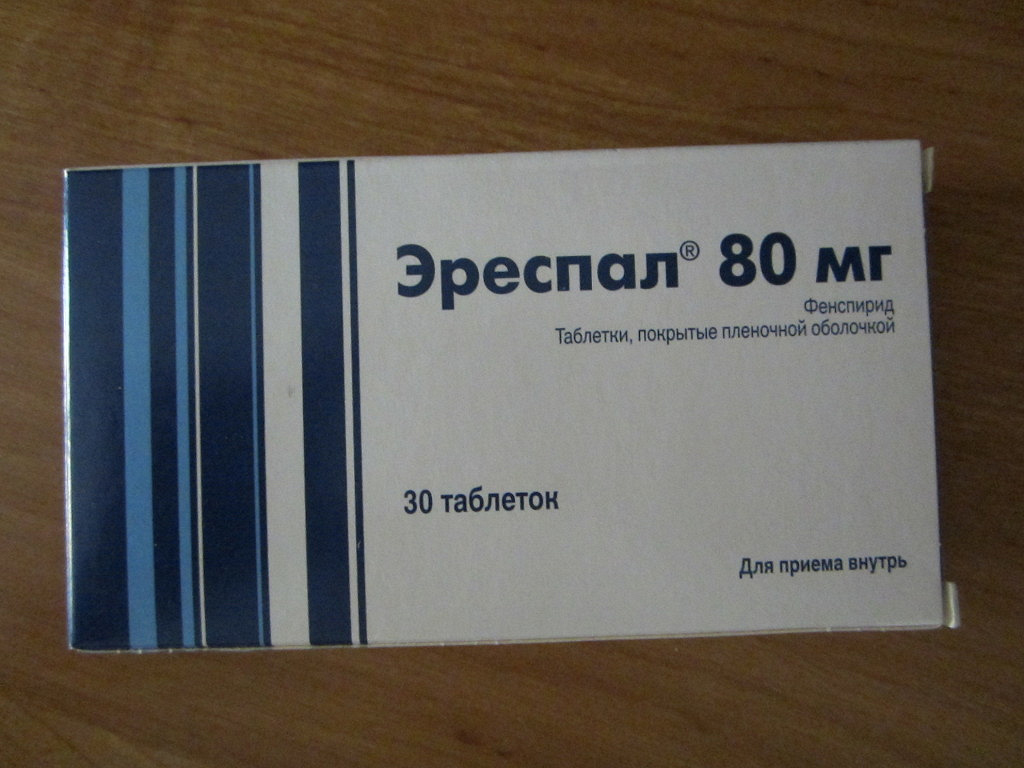

Эреспал детям